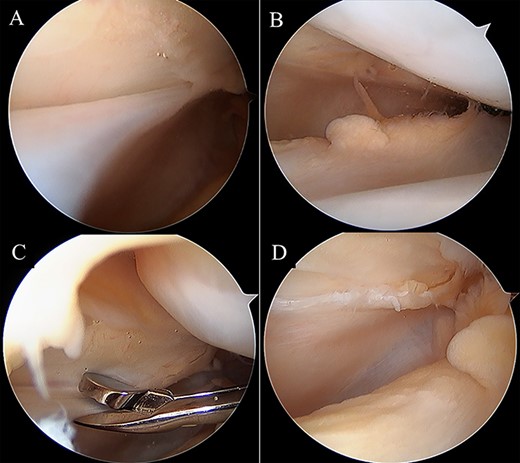

Two months postoperatively, the patient presented with the pain in the medial margin of the patella during walking and knee extension, and the pain continued when she was allowed to start rhythmic gymnastics at 6 months postoperatively. There was no evidence of swelling, crepitus and ROM restriction, and her apprehension sign was also negative. Pain was relieved by an intra-articular xylocaine injection. Postoperative MRI showed no clear injury to the cartilage of the medial PF joint, and the medial PF joint space and the size of the medial plica were almost the same as before surgery (Fig. 2). Based on these findings, left medial plica syndrome was suspected. Although the patient underwent conservative treatment consisting of analgesics and physiotherapy, there were no signs of improvement, and consent was obtained for undergoing arthroscopic surgery at 8 months after the initial surgery. Intraoperative arthroscopic findings with probing confirmed an unenlarged but hardened and thickened medial plica (Fig. 3). No injury to the patellar and femoral cartilage was observed. The synovial plica was considered the main cause of pain, and we performed a partial resection of the medial synovial plica. The pain and the tenderness at the medial margin of the patellar during walking and exercising had gradually improved after surgery. The Lysholm scale improved from 85 to 100 points. At 2 years postoperatively, the patient has currently no pain in the medial side of the patella, negative apprehension sign. She has returned to play in rhythmic gymnastics.

Intraoperative arthroscopic views. Medial synovial plica with a tight and hypertrophic margin (A). No injury to the patellar and femoral cartilage was observed (B). The synovial plica was partially removed with oval forceps (C). Image after removal (D).